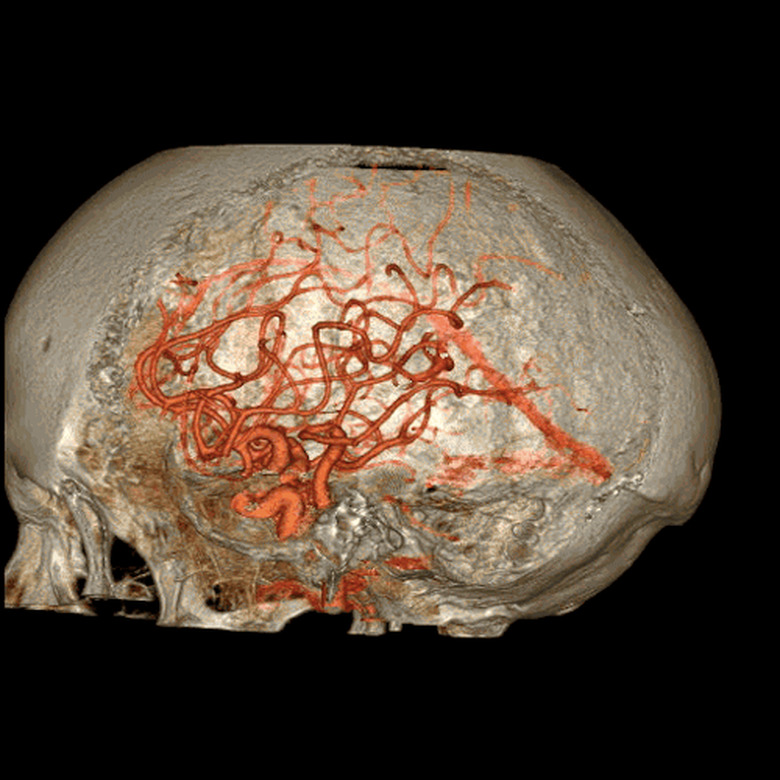

Few people enjoy having a CT scan. In a bleak hospital room, you have to lie flat on your back as a huge circular scanner shoots focused X-rays through your flesh and bones. The entire process can feel a little intimidating, which is why GE Healthcare has come up with the Revolution CT: a whisper-quiet and super-fast scanner that could make medical appointments a little quicker and less stressful for patients. The new machine, which is being trialled by the West Kendall Baptist Hospital in Florida, can capture an entire heart in a single beat, where each rotation takes just 0.28 seconds. That speed, combined with better contrast detection and noise reduction, could also reduce the doses of radiation required in each scan, potentially easing people's fears. In addition, none of these advancements should compromise the quality of the final 3D images — to prove its point, GE Healthcare has released some kinda gross, but undeniably beautiful GIFs of people's innards.

[Image Credit: GE Healthcare]